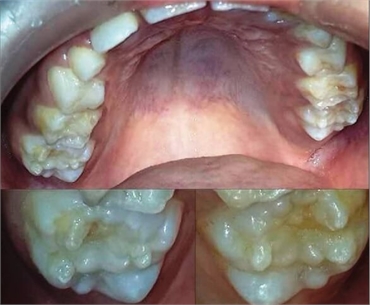

With mulberry teeth, the first molars are dwarfed by small occlusal surfaces and often have disorganized globular projections. The roughened surfaces of teeth is reminiscent of mulberry fruits with many small bumps, hence the name.

With mulberry teeth, the bumpy surface of the tooth increases the risk of cavities. For this reason, many dentists recommend crown restorations for mulberry teeth. Dental crowns will help strengthen teeth and improve aesthetic appearance. It is important to speak to a dentist about which treatments might work best.